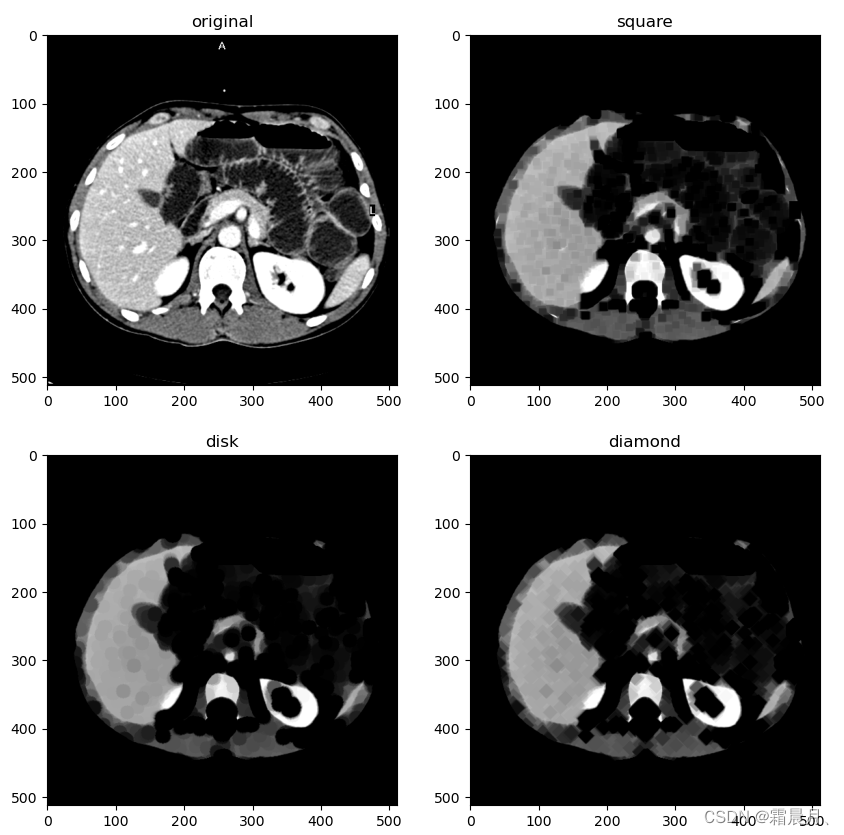

不同类型的核腐蚀

selem = square(5) #square(2) # #square(4) #disk(6)

from skimage.morphology import disk, square, diamond